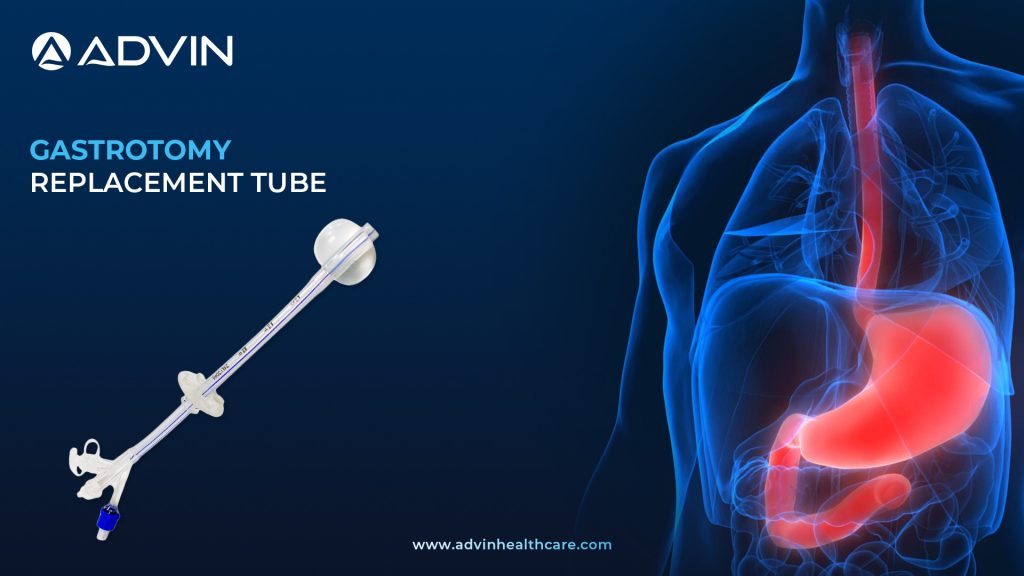

Gastrostomy Replacement Tubes in Modern Enteral Nutrition Care

Gastrostomy Replacement Tube A Gastrostomy Replacement Tube is used to deliver nutrition directly into the stomach of patients who cannot eat by mouth. It is inserted through an existing gastrostomy stoma and can be replaced when the original feeding tube is removed or no longer functional. These tubes are designed...